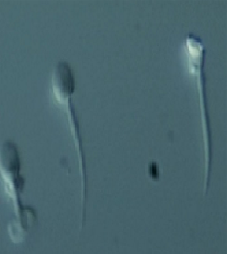

Globozoospermi (Round Head Sperm)

Globozoospermi terimi ilk defa 1965 yılında Myhöfer tarafından tanımlandı. 1971 ve 1973 yıllarında Schirren ve Holstein tarafından akrozom yokluğu olarak tanımlanmıştır. Spermiyogenez (sperm olusumu) sırasında Golgi cisimciğinden gelişen akrozomal vezikülün yokluğu ve eşlik eden cytoskeletal (hücre iskeleti) yapı problemleri nedeniyle sperm başı yuvarlaktır. Sperm kromatinleri kompakt haldedir. Histon ve intermediate proteinlerin oranı normal spermlere kıyasla yüksektir, protamin oranı düşüktür. Boyun yapısı düzensizdir. Nükleus (çekirdek) ve boyun etrafında sitoplazmik dropletler gözlenir. Semen analizi konsantrasyon ve motilite(hareketlilik) bakımından çoğunlukla normaldir. Akrozom yokluğunun sebepleri konusunda farklı görüşler mevcuttur. Akrozomun nükleustan ayrı geliştiği ve artık sitoplazma ile birlikte Sertoli içinde kaldığı gösterilmiştir. Caudal manchette yokluğu ve Kalicin proteini yokluğu yuvarlak baş yapısına sebep olan iskelet problemleri olarak gösterilmiştir. Globozoospermi’nin 2 alt tipi tanımlanmıştır:

- Tip I : Kromatin sferik(küresel) olarak dağılmıştır ve akrozom tamamen yoktur. Spesifik proteinaz olan akrozin ve bir hücre iskelet proteini olan kalisin yoktur . Baş içerisinde büyük vakuoller gözlenir.

- Tip II : Koni şeklinde bir nükleusla (çekirdekle) beraber bir miktar akrozom mevcuttur. Baş etrafında sitoplazmik kalıntılar göze çarpar. Motilite (hareketlilik) problemi mevcuttur.

Tip I Tip II

DNA fragmantasyon oranının yüksek olduğu gösterilmiştir. Oosit (yumurta) aktivasyonu için gerekli faktörlerin eksik olması nedeniyle oositin mayozu tamamlayamaması ve sperm kromatininin oositin kromozom kondensasyon (yoğunlaşma) faktörleri tarafından engellenmesi nedeniyle döllenme başarısızlığı yüksektir (%30-60). Kimyasal aktivasyon ve elektriksel aktivasyon uygulanması ile oosit aktivasyonunun döllenme oranlarını arttırdığı gösterilmiştir ve bu durumun sperm sentrozom fonksiyonunda bozukluk olusturdugu saptanmıştır ancak genetik mekanizması henüz açıklanamamıştır.